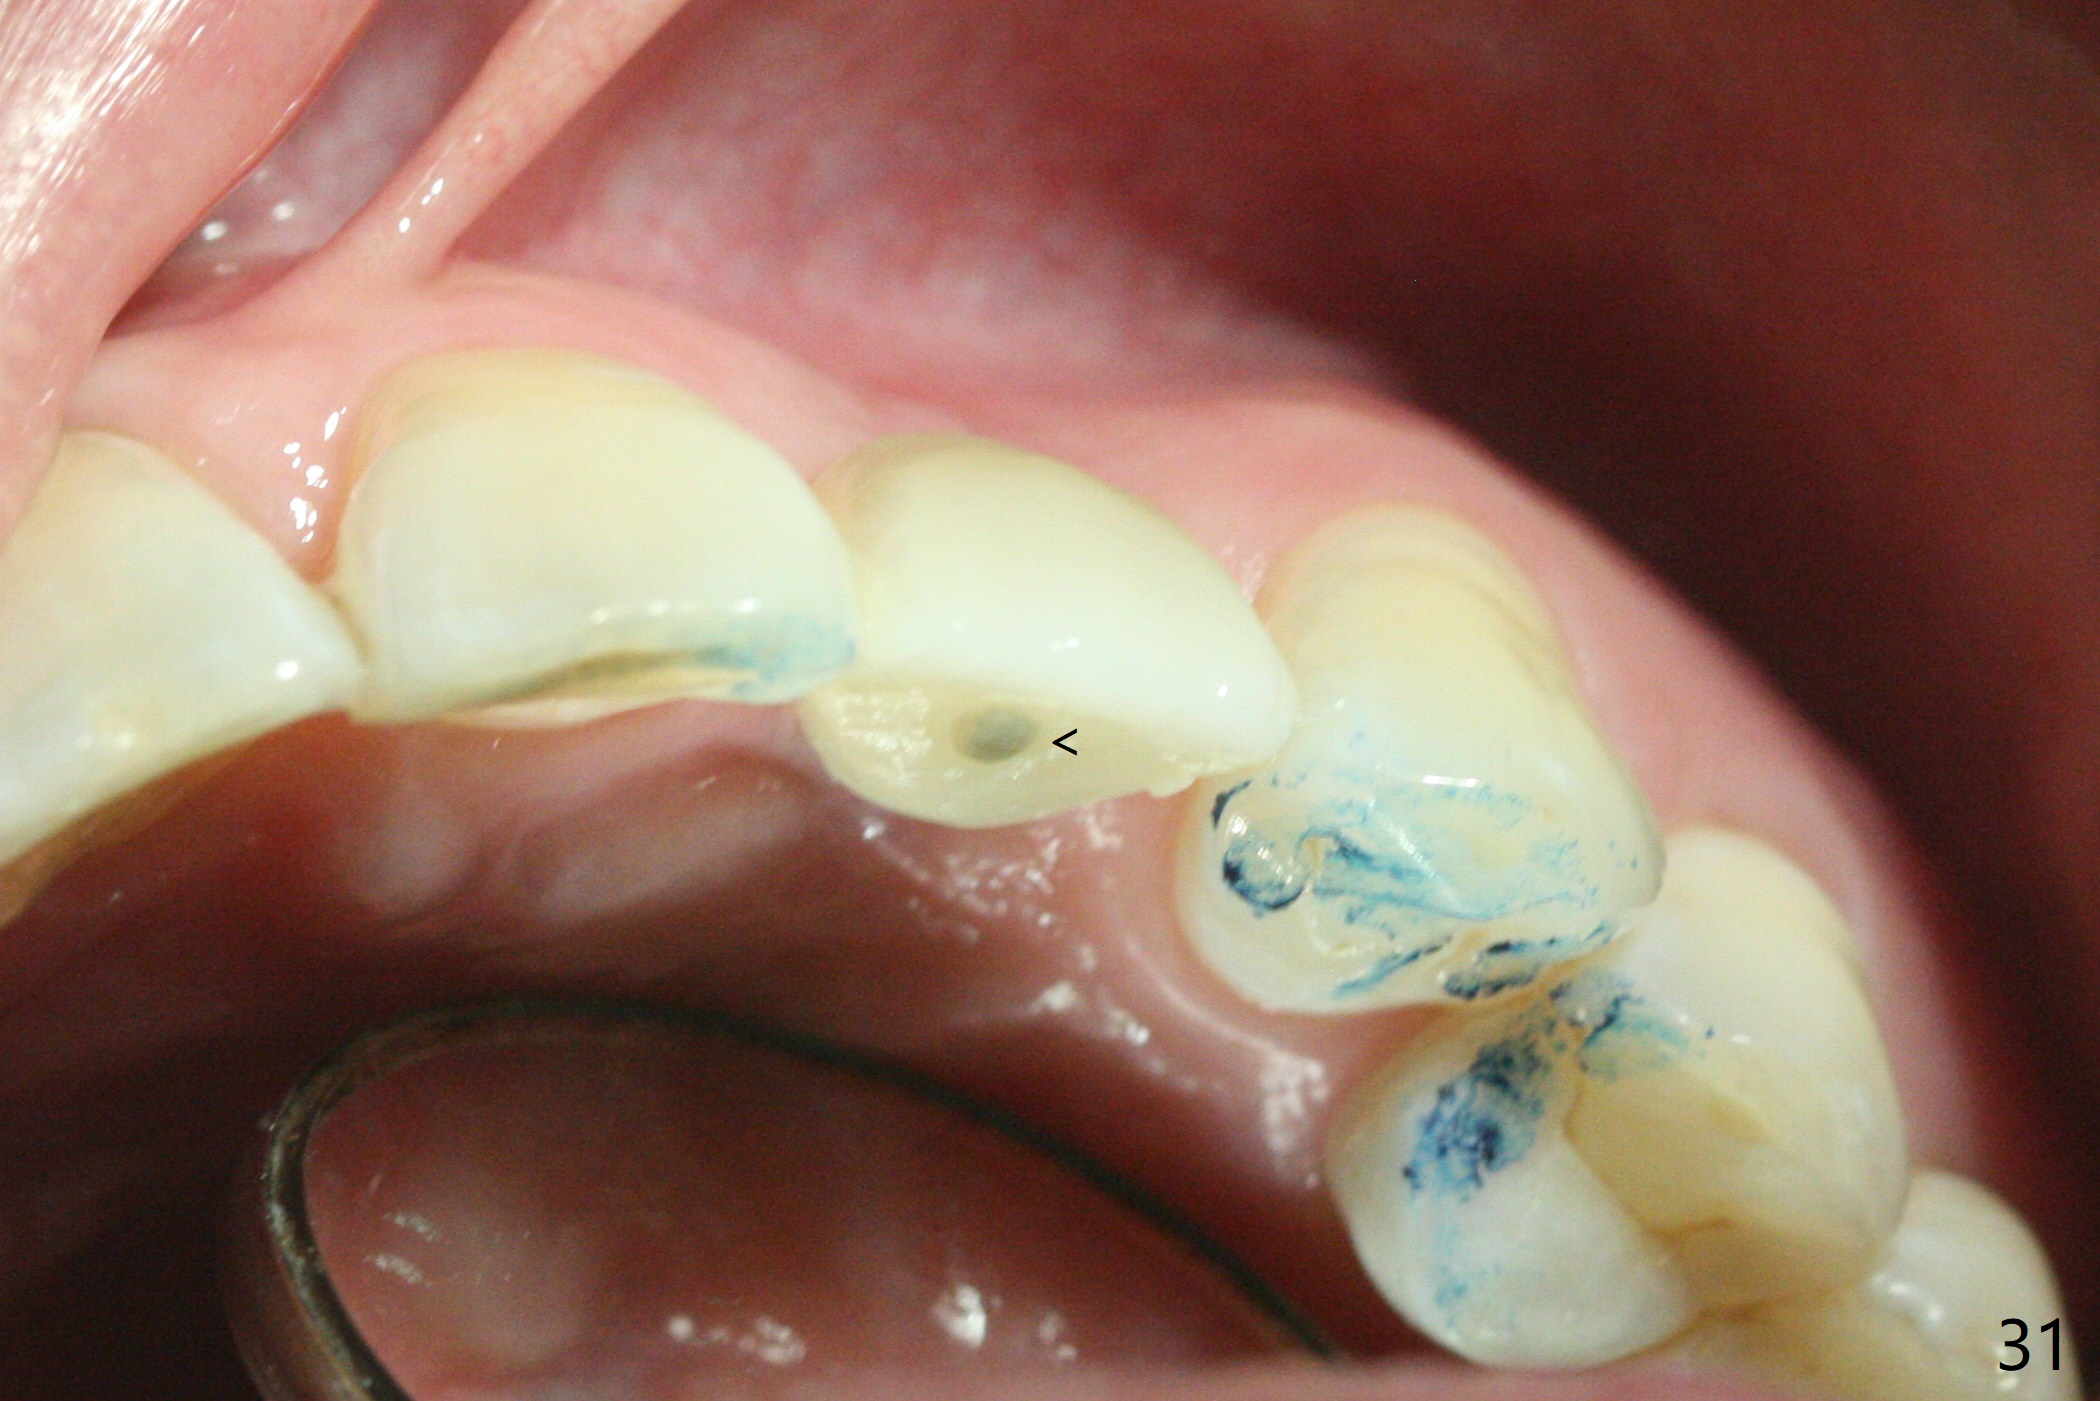

病人回来带来瘘道(图一),不过不会增加难度,病牙去除,它便自动消失。尽管颊侧骨壁完全失去,颊侧牙龈仍丰满(图二),为什么呢?第一,因为粗大牙根存在,第二两旁牙齿,牙槽骨撑着帐篷(侧切牙颊侧牙龈),第三,牙冠。为了防止术后牙龈塌陷,尽量不切开,即刻放置植体(牙根);由于前牙缘故,这次植体不能很大,所以植骨必须过度(over grafting),最后即刻制作临时牙冠,撑住牙龈。这就是所谓每个人进入角色。这个牙根有一种先天性畸形:dens in dent (图三(腭侧观):箭头)。尽管腭侧牙根畸形,腭侧骨壁吸收临床上并不严重,所以钻洞仍偏腭侧。当预定最后钻头还在钻洞时,填入大量粘性骨块(图四:*),细长植体还没有完全卡入鼻底(图五),最后好像可以(图六,七)。植体,骨粉入位(图八),最后临时牙冠出场(图九)。尽管植体小,术后一周临时牙冠仍然可以维持牙龈原有形状(emergency profile,图十:箭头(*:树脂强化牙冠固定))。图十一以不同角度显示瘘道缩小。术后三周取出有些松动的临时牙冠,骨粉虽然还没有被肉芽组织整合,但是显得正常,周围牙龈健康(图十二)。术后4个月牙龈形态正常(图十三),没有触痛;颊侧骨板轻度凹陷(图十四);骨粉仍在原位(图十五)。术后7个月骨粉仍在原位(图十五,十六,但是冠部密度减低(可能骨粉流失,需要牙周或者树脂敷料保护)),没有螺纹暴露。但是牙冠边缘暴露,说明牙龈收缩(图十七,与图十三对比),颊侧骨板仍塌陷(图十八)。插入龈线取得多个目的:修整基台边缘,取模,颊侧牙龈推向颊侧,有利于即将衬里牙冠龈缘进入龈下(图十九)。取模后牙冠边缘(图二十:<)衬里,然后修整,变窄,以便插入龈下,促进颊侧牙龈下降(图二十一,二十二)。术后8个月牙冠粘固前牙龈健康(图二十七,八),牙冠(图二十九)固位后,病人满意(图三十),咬合调整(图三十一),注意腭侧粘固粉流出通道(<)。